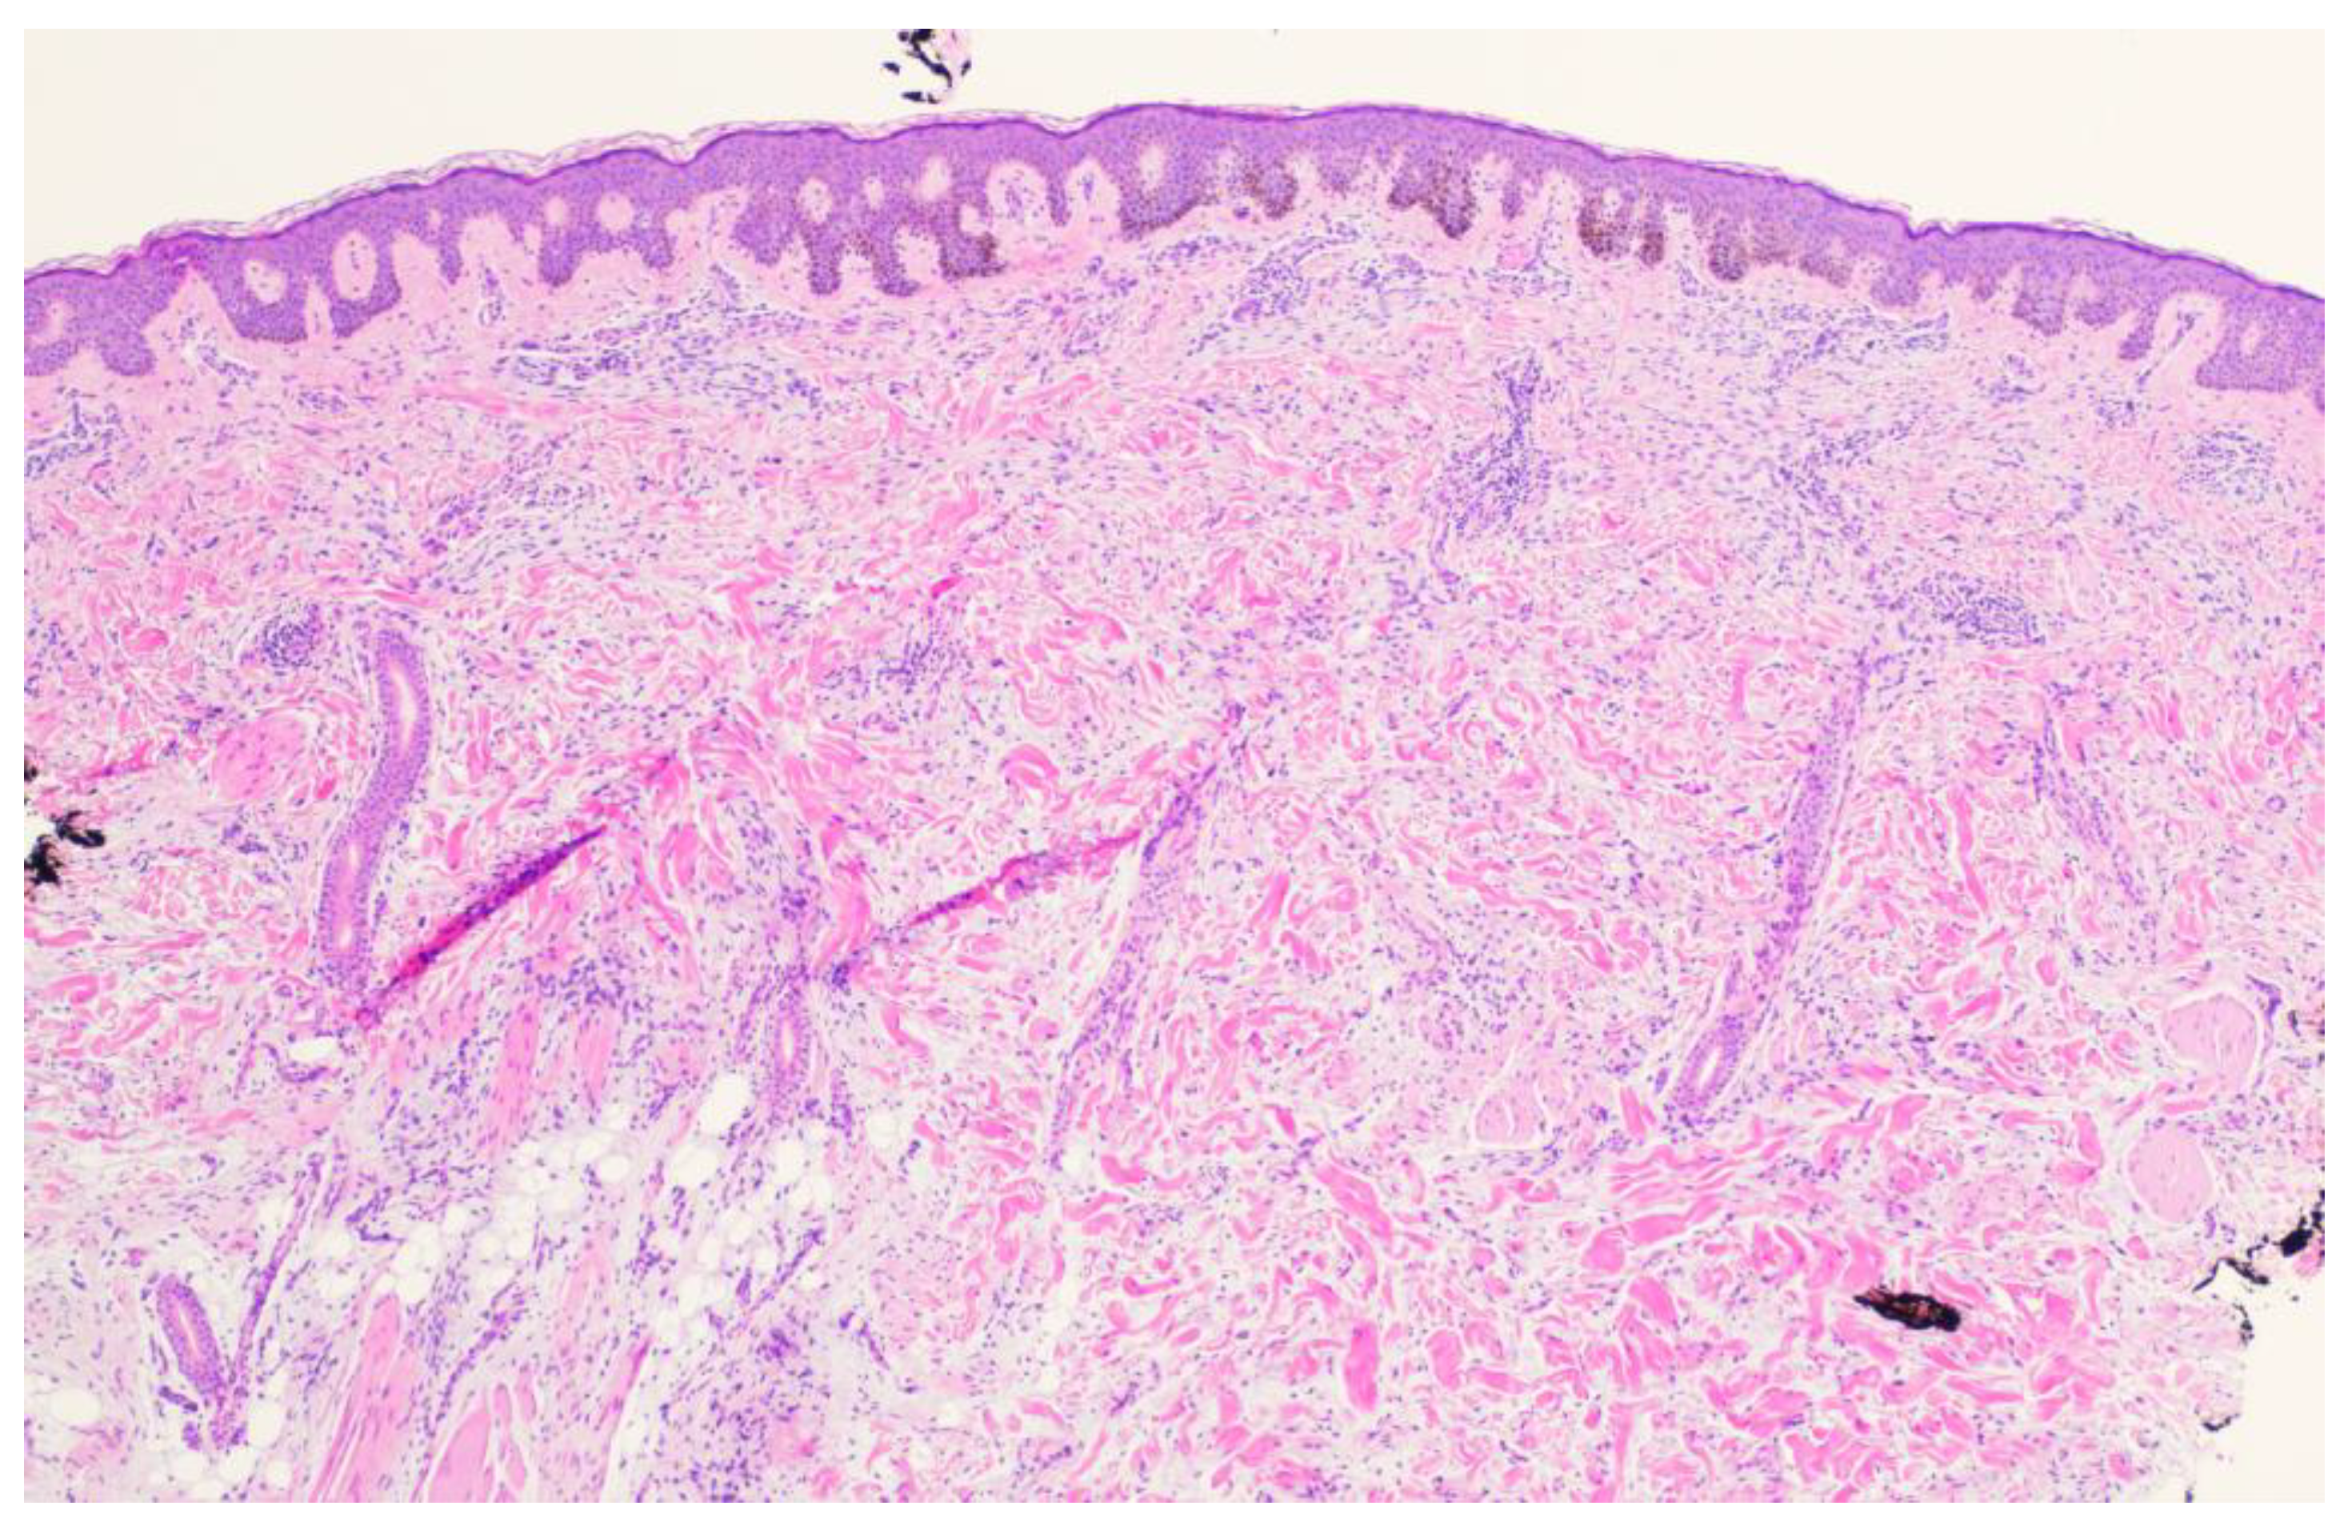

Figure 1). A punch biopsy was obtained and revealed atypical myxoid spindle cell neoplasm and involved margins with overlying mildly atypical compound melanocytic nevus. The specimen also displayed CD34 positivity (histopathology displayed in

Figure 2,

Figure 3,

Figure 4,

Figure 5,

Figure 6,

Figure 7,

Figure 8 and

Figure 9). A diagnosis of spindle cell lipoma was reached, and wide local excision with 2 cm margins was performed and subsequent pathology revealed clear margins.

Histopathologically, the presence of an atypical myxoid spindle cell neoplasm with CD34 positivity further complicated the diagnosis. The biopsy also revealed an overlying mildly atypical compound melanocytic nevus, which is an unusual finding in SCL and raised concerns about a potential collision tumor or a misdiagnosis.